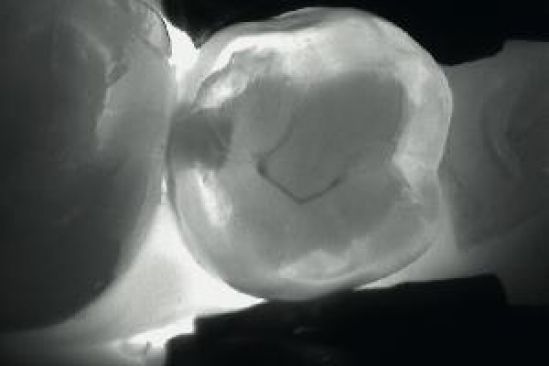

El sistema utiliza el diente como un conductor de luz, una cámara de video captura esa luz y la transmite a una pantalla en la que, si hay caries, aparecen en forma de puntos negros. Al no utilizar radiación, el sistema se puede usar tantas veces como sea necesario. DIAGNOcam trabaja con dos fuentes de luz que traspasan el diente desde los costados y los puntos cariados se ven como manchas oscuras.

Utilizando la transiluminación, el esmalte aparece reflejado con un aspecto cristal. A diferencia de una estructura dental sana, la caries absorbe mayor luz y permanece oscura, permite de esta manera determinar la ubicación y la extensión de la caries sin necesidad de rayos X.